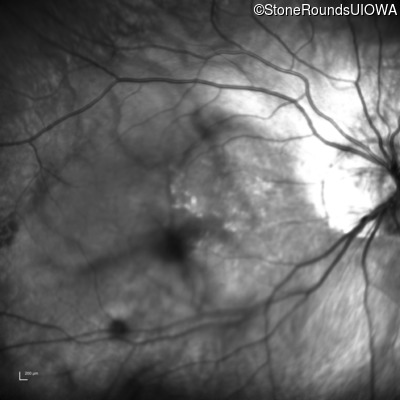

AR CSNB, normal fundus (IA2fiii)

Age at visit: 16 years

This 16 year old male has had poorer vision in dim light than his siblings since childhood. He has also been very myopic since childhood and is currently wearing -14.00 diopter spectacles. The maximum combined response of the electroretinogram reveals a selective loss of the b-wave.